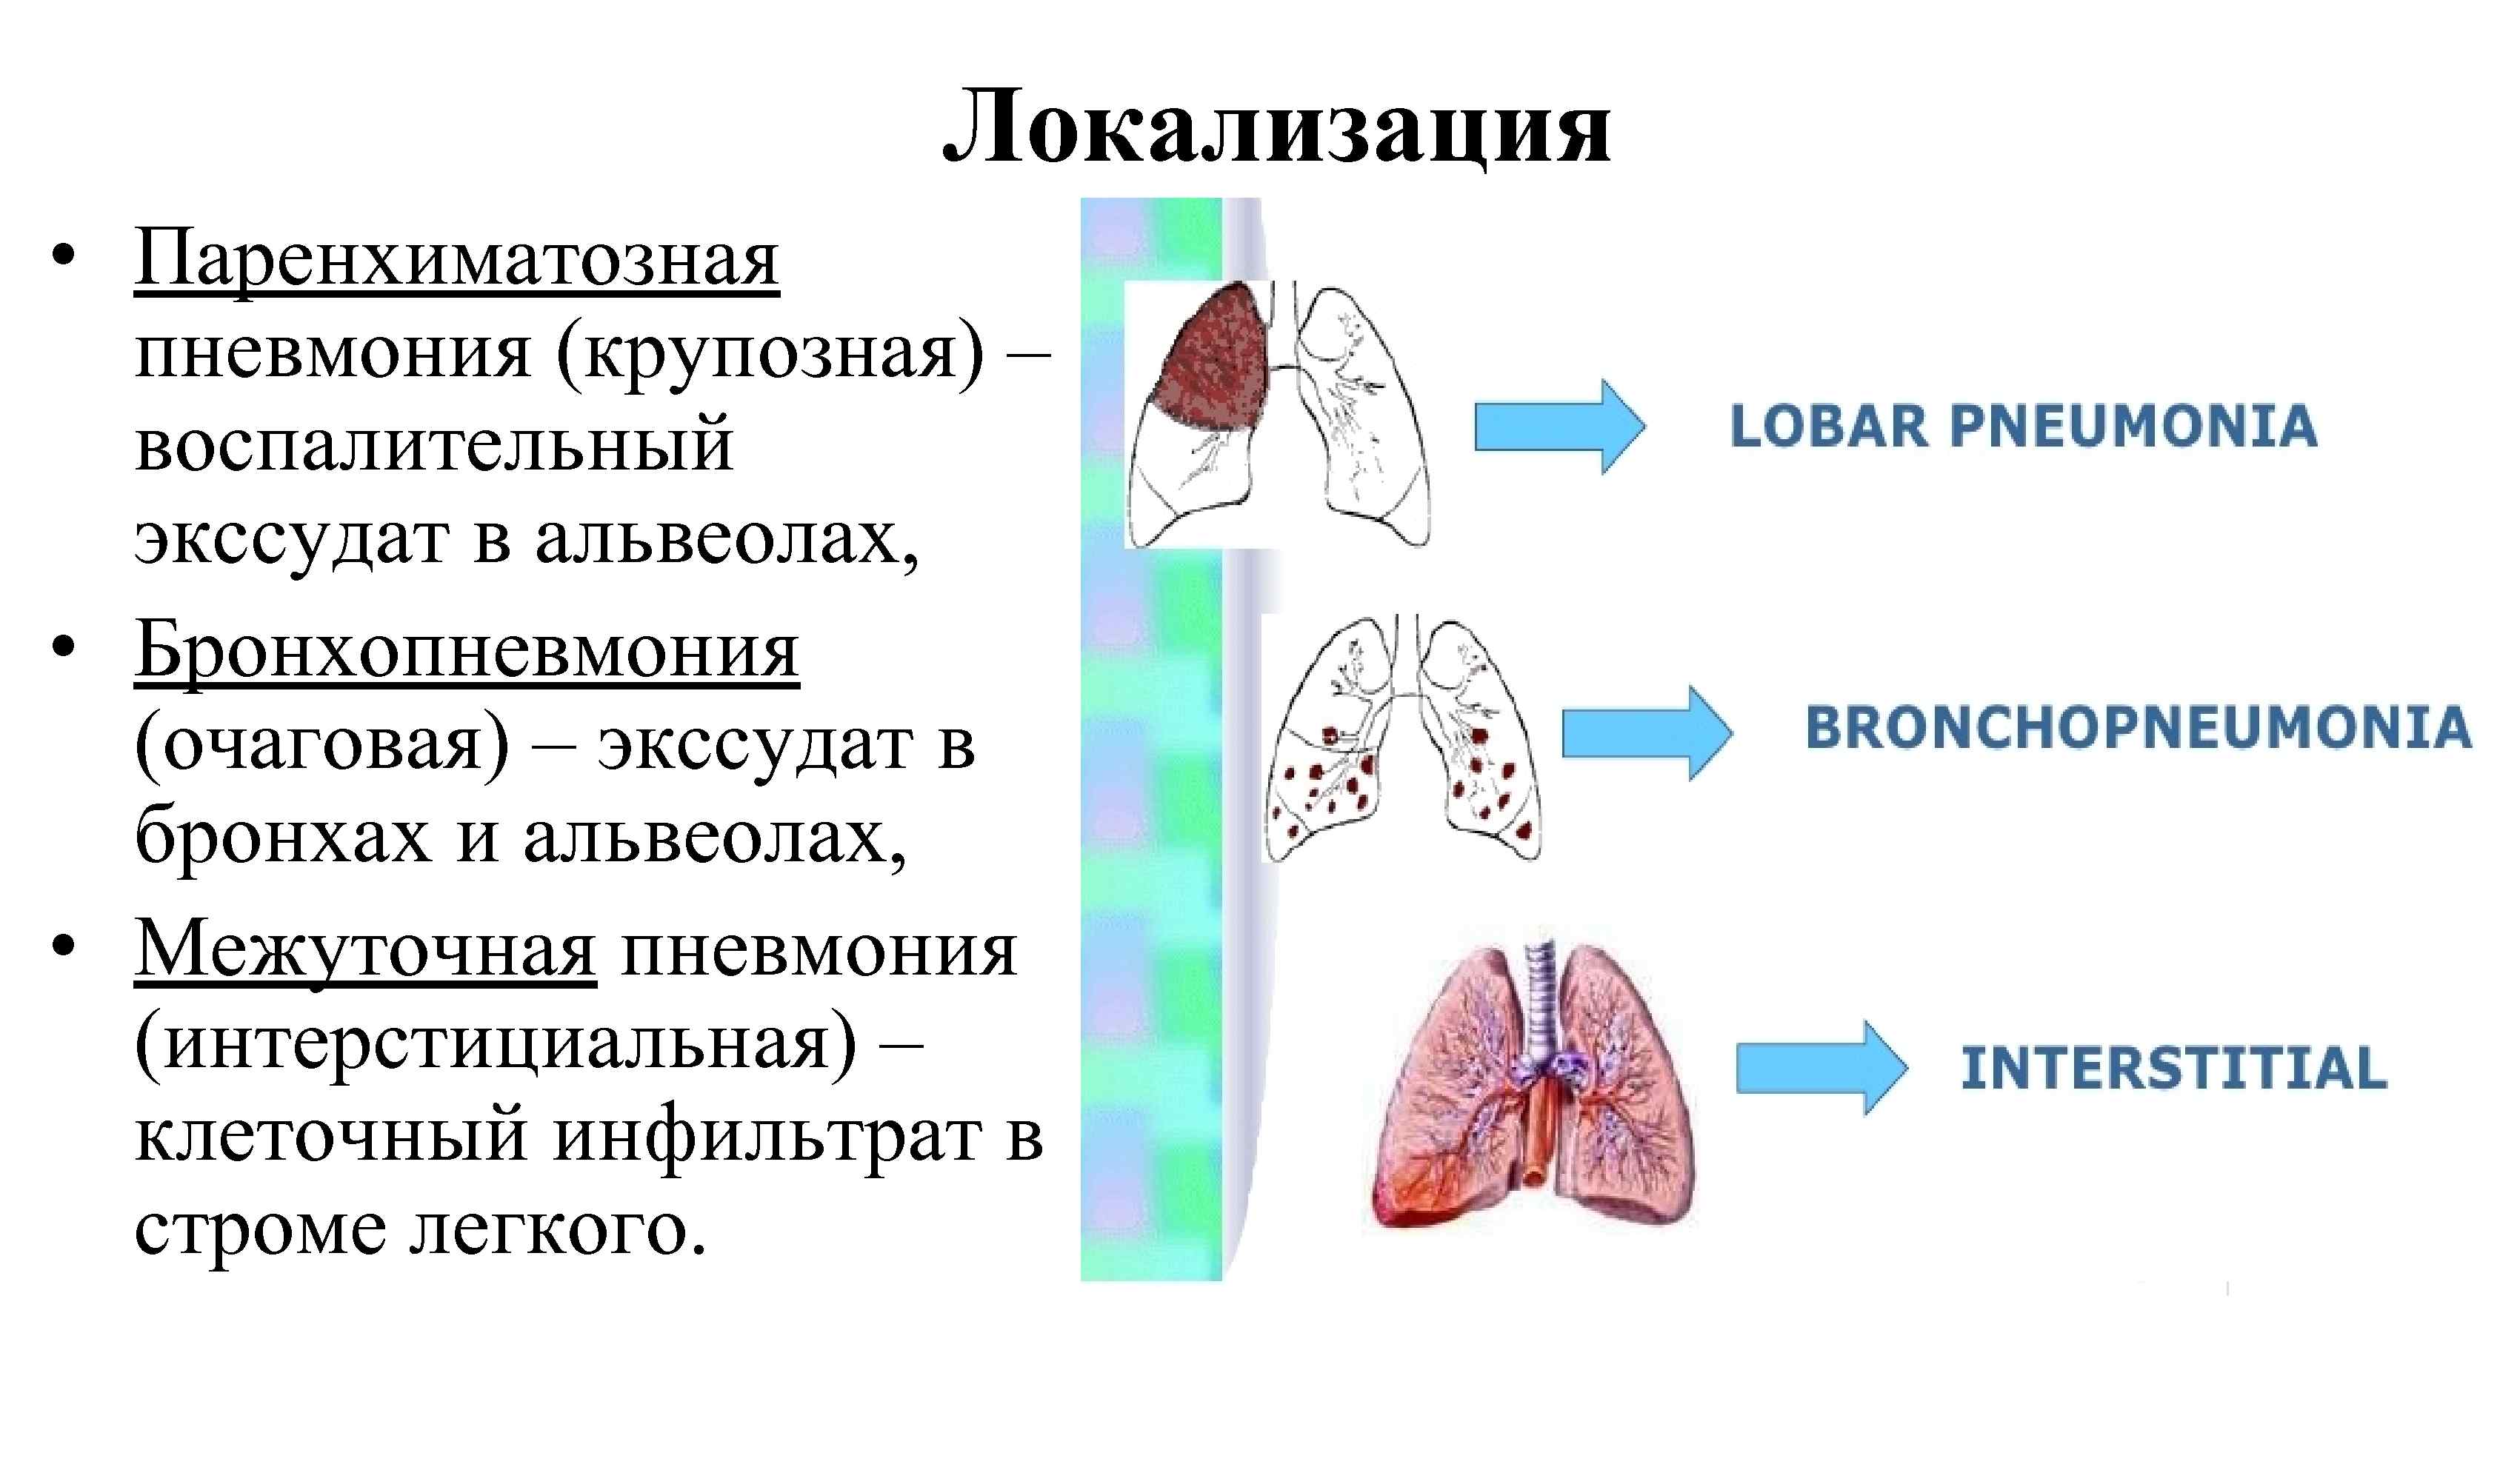

Пневмония - это серьезное заболевание легких, которое может быть вызвано различными причинами, включая бактериальные, вирусные и грибковые инфекции. Для того чтобы наглядно показать симптомы, диагностику и лечение этого заболевания, картинки могут быть очень полезны.

Картинки с симптомами пневмонии

В этом разделе представлены изображения, демонстрирующие различные симптомы пневмонии, такие как кашель, одышка, боль в груди и повышенная температура. Эти картинки могут быть использованы для обучения и презентаций в области медицины и здравоохранения.